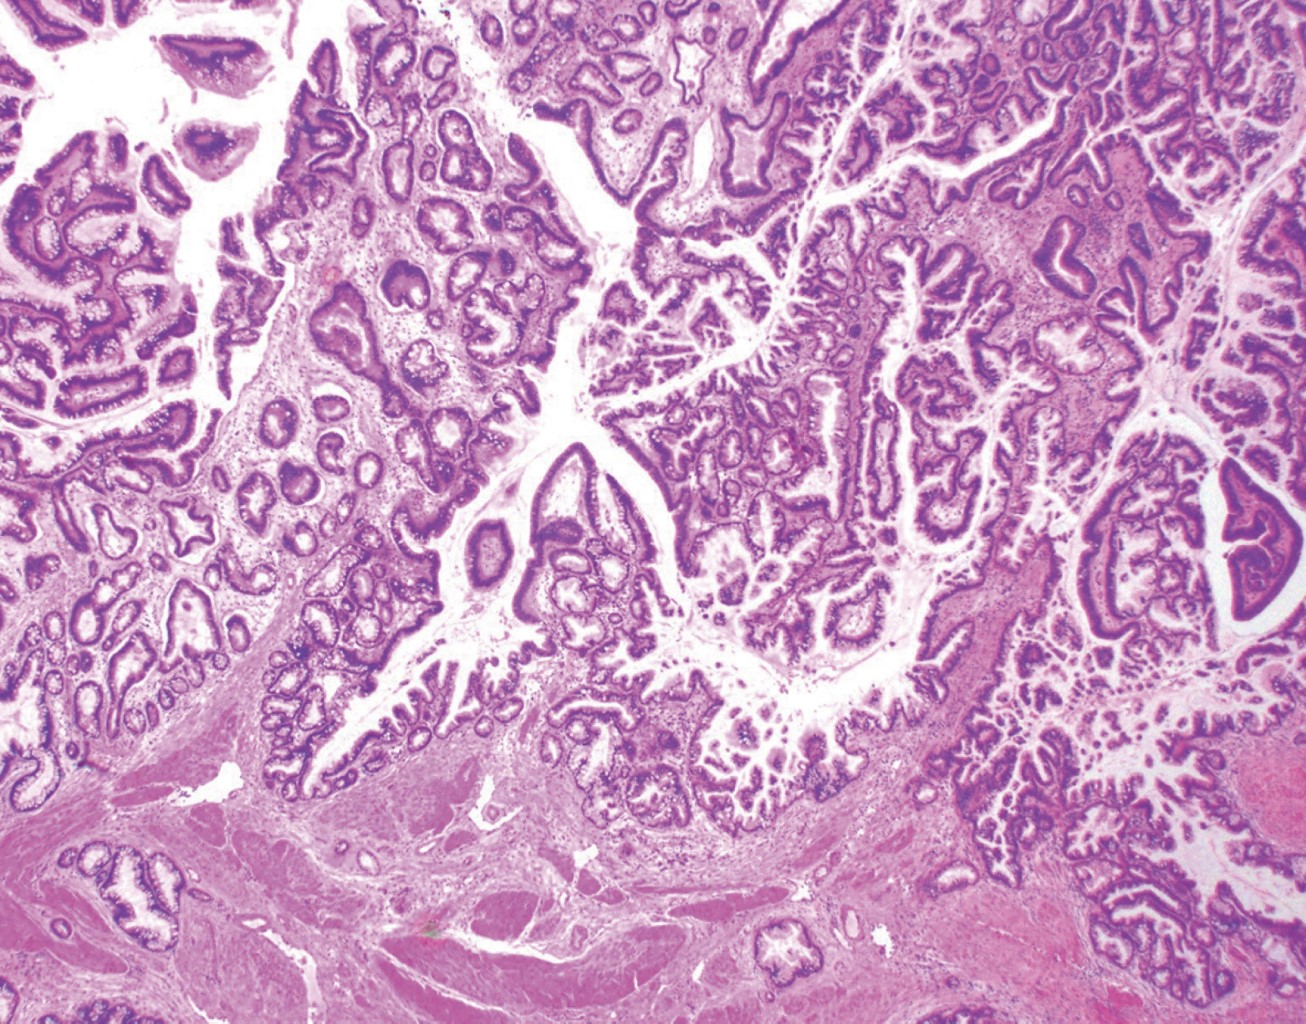

A 64-year-old male began his illness with jaundice and denied other symptoms. It is noteworthy that he had it for at least three days before he arrived at the emergency room; his physical examination was without alterations, and his lab tests showed total bilirubin of 25 mg/dl, direct bilirubin of 22 mg/dl, alkaline phosphatase 235 IU/l, gamma-glutamyl transferase 157 IU/l, creatinine 2.5 mg/dl, and the rest of the test were within normal limits. An abdominal ultrasound was performed, which reported an ill-defined gallbladder and dilatation of the biliary tract of 19 mm (Figure 1); a 12 mm bile duct stone was observed in the common bile duct. The diagnosis of choledocholithiasis was done. Tumor markers were requested, with a report of CA 19-9 > 8,000 IU; cholangioresonance was performed, which showed bile duct dilatation (bile duct) of 20 mm and a 16 mm stone at the level of the ampulla. No morphology of the gallbladder (GBV) was reported. The patient was a candidate for endoscopic retrograde cholangiopancreatography (ERCP), according to the Gastroenterology service. ERCP was performed without being able to extract the lithium, and the patient was scheduled for cholecystectomy with an exploration of the biliary tract; the transoperative examination revealed biliperitoneum, lysis of the GB, a cholecystocoledochobiliary fistula (Figure 2) and a single 15 mm stone; a T probe was placed. Since there was no hepatopancreaticobiliary surgeon a definitive repair was not performed. A transoperative cholangiography revealed passage of contrast material to the duodenum without apparent leakage through the fistulous orifice (Figure 3). The patient had a favorable postoperative evolution; the drainage through a T catheter was an average of 500 ml per day with progressive decrease, with the improvement of hyperazoemia and a urinary flow greater than 0.5 ml/kg/h. A postoperative cholangiography showed no leaks with the passage of the contrast medium to the duodenum. The pathology report revealed a moderately differentiated adenocarcinoma of the gallbladder with muscular infiltration (Figure 4). The patient refused medical treatment and decided to voluntary discharge; he understood and accepted the risks and was lost for follow-up.

On the other hand, GBCA is the most frequent cancer of the biliary tract, 80% concerning cholangiocarcinoma; it is more commonly found in the fundus (60%), body (30%), and neck (10%) or the GB; the most frequent histological type is adenocarcinoma. It is considered invasive when it surpasses the muscularis propria, that is, stages T1a (Figure 4). Frequently, some cases are found with perforation of the visceral peritoneum and invasion of adjacent organs; however, intraoperative diagnosis and radical treatment are only performed in less than 1% of the cases.8-10

Figure 4